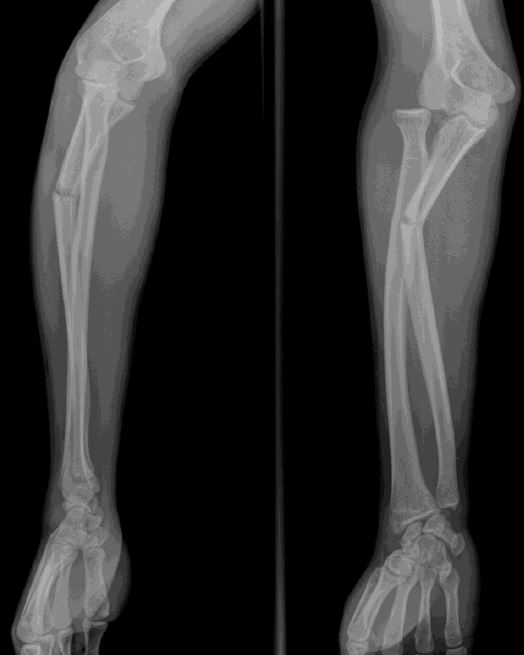

A. Proximal ulnar fracture

B. Radial head dislocation

C. Monteggia fracture-dislocations

D. Galeazzi fracture-dislocations